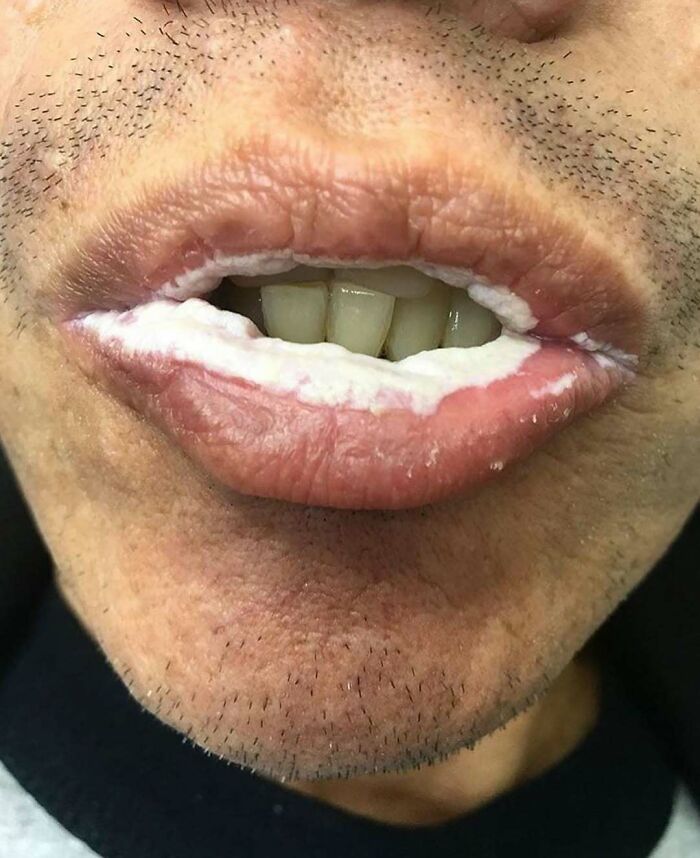

Oral candidiasis, also known as oral thrush, is a condition in which the fungus Candida albicans accumulates on the lining of the mouth.

23-year-old male presented to the emergency department, with rash, mouth sores, and subjective fevers that began after eating fish five days prior. His symptoms started with sores in his mouth and on his lips with penile and anal pruritus. After 24 hours, the patient developed a pruritic rash over his upper extremities, neck, upper back, and palms, as well as two non-painful sores on his penis

On physical examination, he had heme-crusted polycyclic erosions of vermillion lips, buccal mucosa, and labial mucosa.. He was also found to have numerous 2-12 mm erythematous, urticarial, targetoid papules and plaques with central hyperpigmented purple/red duskiness over bilateral palms dorsal hands, upper arms, lateral neck

"Erythema multiforme is an immune-mediated, typically self-limiting, mucocutaneous condition characterised by 'target' lesions. Significant mucosal involvement distinguishes erythema multiforme major from multiforme minor. Episodes can be isolated, recurrent, or persistent. In most cases, erythema multiforme is precipitated by herpes simplex virus (HSV) infection."